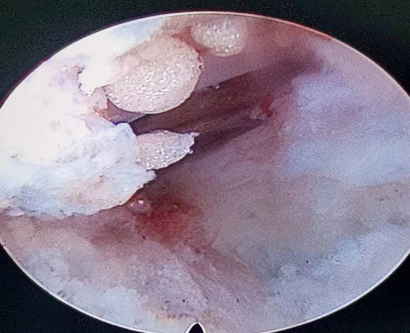

术中所见突出间盘组织

切除突出间盘:见间盘炎性变伴钙化

神经根管走形清晰显露,无压迫、侧隐窝减压彻底